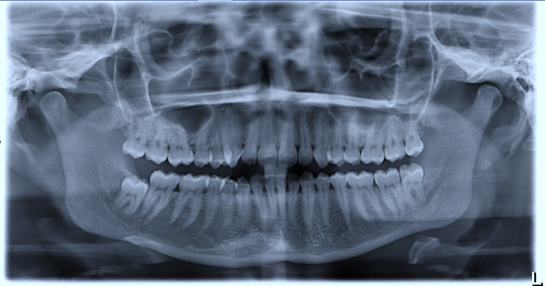

25. (Select ONE OR MORE correct answers.)

Tooth 4.8 is planned for extraction. Which radiographic findings suggest an increase in the degree of difficulty of the extraction?